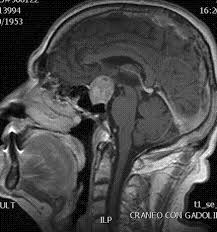

Pemeriksaan dasar yang harus dikerjakaan pertama kali adalah pemeriksaan kandungan hormon pada darah dan pemeriksaan MRI kepala dengan kontras. Selanjutnya bila disertai keluhan pandangan mata kabur dan menyempit pasien akan akan menjalankan pemeriksaan tes lapang pandang mata.

Tumor mikroadenoma non-fungsional (tidak mengalami permsalahan hormon dan ukuran kecil) sering ditemukan secara tidak sengaja pada proses MRI. Pada jenis ini hanya akan dilakukan observasi ketat dengan mri kepala dengan kontras per 3 bulan atau 6 bulan sesuai perkembangan kondisi pasien. Sedangkan untuk ukuran tumor yang besar hingga menyebabkan gangguan penglihatan harus segera dilakukan pembedahan. Teknik bedah dapat berupa bedah mikro atau endoskopi lewat hidung. Prosedurnya sangat tergantung dari bentuk, ukuran serta posisi tumor terhadap struktur vital dalam otak.